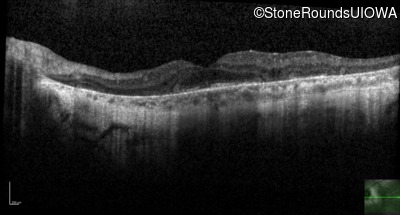

This 46 year old man first had difficulty driving at night in his mid-thirties. Clinically focused genetic testing for Choroideremia was negative.

| XL Choroideremia | CHM | Insertion of 212.3kb of Chr. 3 in intron 2 (IVS2+15,016 ins 212.3kb) | XL |